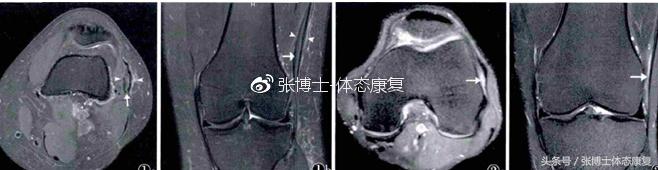

髂胫束摩擦综合征的诊断

MRI检查有助于髂胫束摩擦综合征的诊断。患者采取仰卧位、膝关节取伸直位,可看到髂胫束韧带部分有增厚,高信号,表明有炎症。